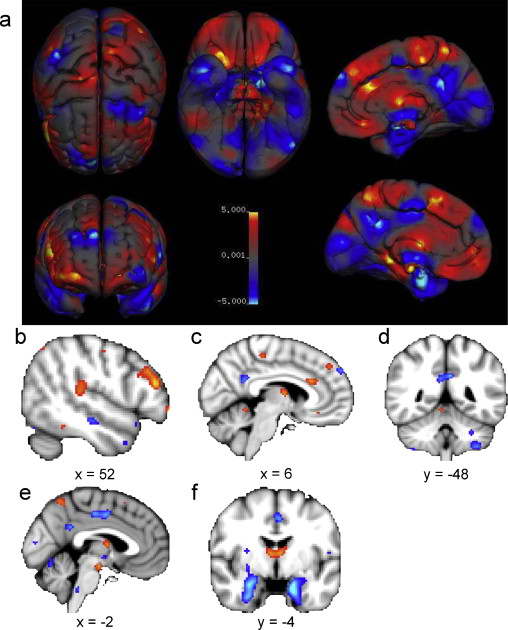

灰质密度差异:

女性>男性为红色,男性>女性为蓝色

整体来看,男性的边缘系统灰质具有更大的体积和密度,女性的语言系统相关灰质具有更大的体积和密度。